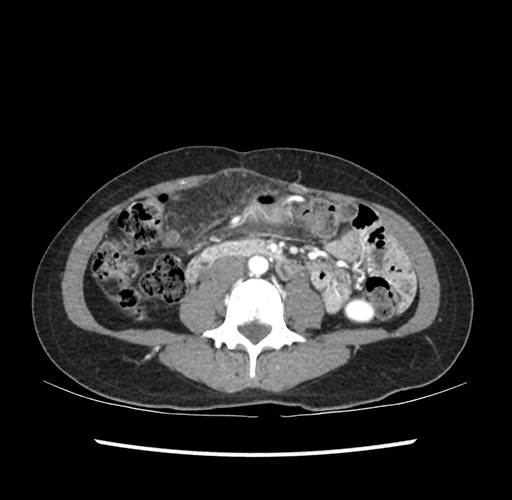

Imaging Analysis

Look through the patient's CT scan to identify any areas of concern for the necessary procedure.

Based on your CT findings, which issue(s) would give reason for "planned slowing down moment(s)" in this case?